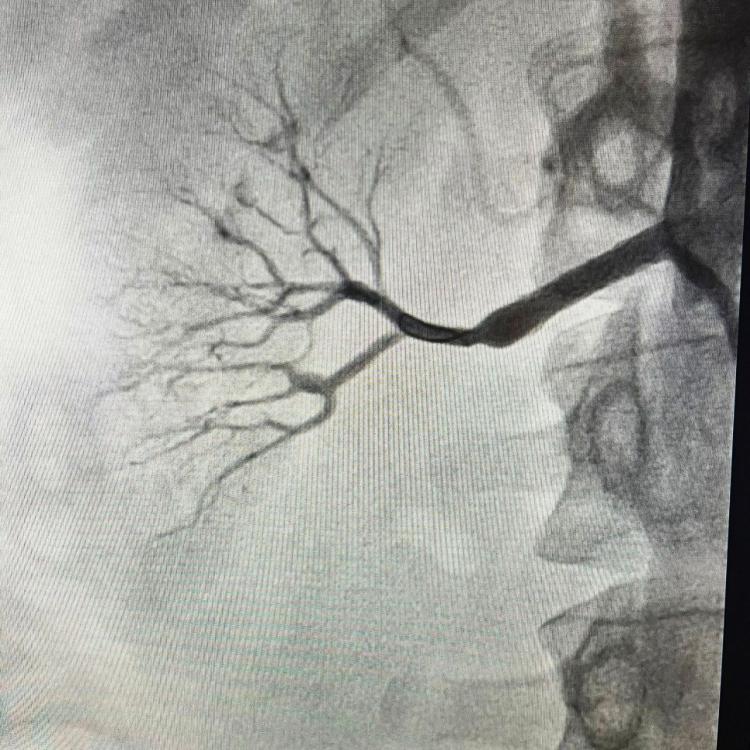

Молодая пациентка обратилась в Региональный сосудистый центр с внезапными гипертоническими кризами. Компьютерная томография выявила практически полное перекрытие правой почечной артерии разросшейся фиброзной тканью.

«Это первый случай болезни Ормонда в нашей практике, – отметил рентгенэндоваскулярный хирург Вячеслав Воробьев. – После углубленного КТ-исследования, подтвердившего сохранность функции почки, было принято решение о немедленном хирургическом вмешательстве. Без операции девушка могла лишиться органа».

Для проведения сложной процедуры специалисты заказали индивидуальный стент, способный выдержать высокое давление. Операцию, длившуюся около получаса, успешно выполнил заведующий отделением рентгенохирургических методов Никита Грачев.